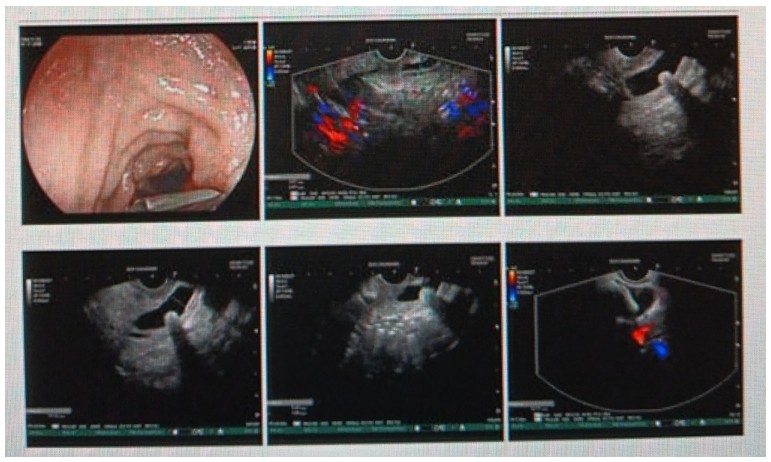

消化內(nèi)科肝病亞??茍F(tuán)隊(duì)詳細(xì)討論,分析患者情況后,取消了周女士的肝穿刺活檢檢查,建議患者先行超聲胃鏡下膽胰掃查。在內(nèi)鏡醫(yī)師第三只眼——超聲胃鏡的掃查下,發(fā)現(xiàn)引起周女士肝功能受損的罪魁禍?zhǔn)?/span>原來(lái)是膽總管末端結(jié)石!伍友興主任醫(yī)師帶領(lǐng)團(tuán)隊(duì)給予患者行ERCP下取石后,周女士未再出現(xiàn)腹痛,肝功能恢復(fù)正常。

無(wú)獨(dú)有偶,劉先生也為反復(fù)出現(xiàn)肝功能受損到多家醫(yī)院就診檢查,未能找到原因,來(lái)到衡陽(yáng)市中心醫(yī)院消化內(nèi)科就診,希望能在肝穿刺活檢下得出病因。在行肝穿刺活檢之前,醫(yī)生建議劉先生行超聲胃鏡膽胰掃查,發(fā)現(xiàn)引起劉先生反復(fù)肝功能受損原因,亦是膽總管結(jié)石引起,在ERCP術(shù)取石術(shù)后,患者肝功能恢復(fù)正常,未再出現(xiàn)異常情況。

張丹霞主任醫(yī)師介紹,超聲內(nèi)鏡通過(guò)胃十二指腸自然腔道,可以將探頭貼近相應(yīng)的位置,近距離的觀察胰腺及膽道系統(tǒng),準(zhǔn)確捕捉到直徑小于5毫米的胰腺異常病灶及膽道系統(tǒng)病灶。而體表B超常受皮膚、脂肪或腸道氣體干擾。CT或磁共振檢查只能提供靜態(tài)圖像,且對(duì)膽胰管陰性結(jié)石或是未引起明顯膽管梗阻性的結(jié)石檢查有局限性,因此對(duì)于有輕微腹痛合并肝功能受損的患者,建議常規(guī)行超聲胃鏡下膽胰掃查。超聲胃鏡、腹部彩超、腹部CT、腹部MRI同為診斷膽管細(xì)微病變的四架馬車,在膽總管結(jié)石診斷方面,超聲胃鏡膽胰掃查同ERCP一樣,是敏感性高、特異性強(qiáng)的診斷方法。超聲胃鏡發(fā)現(xiàn)可疑病變,可以完成穿刺活檢,還可行囊腫穿刺引流、膽管減壓、消融術(shù)等。